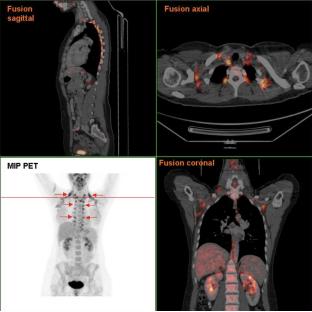

随着年龄的增长,棕色脂肪细胞会逐渐减少 ,以至于人们一度以为成人没有棕色脂肪细胞。多亏了造影技术的不断发展,科学家才通过PET/CT扫描发现成人的颈部、锁骨上方、脊椎边缘和肾脏周围仍然有棕色脂肪细胞。

CT/PET所显示的成年女性棕色脂肪组织

图源:wiki